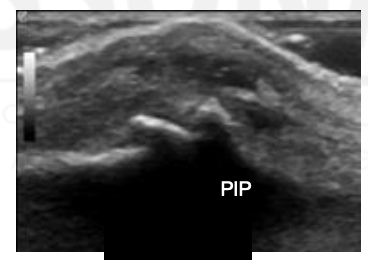

What view is this?

PIP

Synovium

Extensor Tendon

Proximal Phalanx

Middle Phalanx